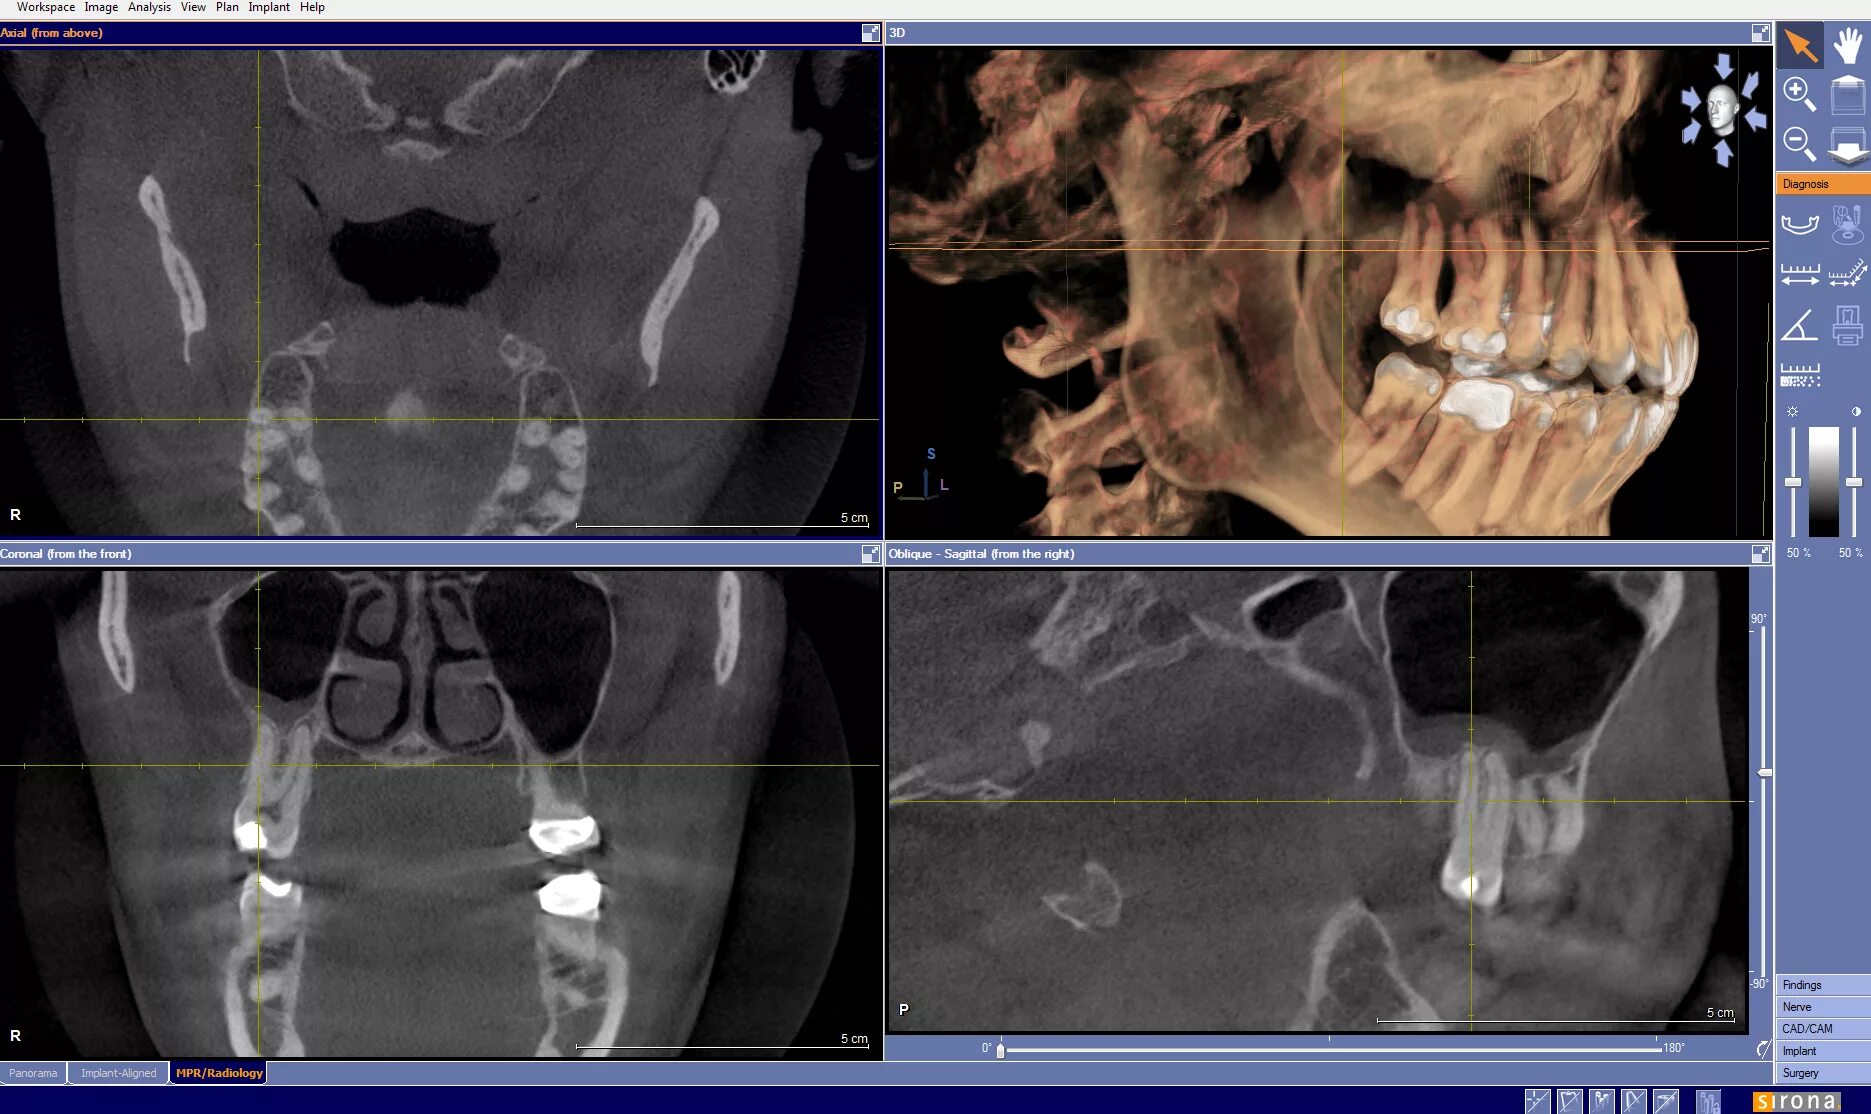

Кл кт